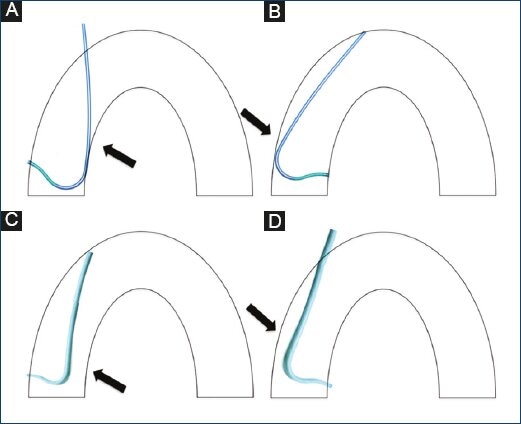

An additional backup catheter (Voda, XB, and EBU) may improve procedural success with different modalities. However, there have been limitations with treating left main lesions, short left main with ostial circumflex lesions and right coronary lesions (Fig. 3). The Amplatz right catheter facilitates ostial access to right proximal, mid-, or distal coronary lesions. However, when significant tortuosity is present, it may be difficult to stabilize or advance the catheter. Furthermore, it does not offer adequate support, stability or control when treating the left coronary system. The Amplatz left catheter may provide good support and stability to the RCA and may ease balloon and stent placement. Nevertheless, when treating proximal and ostial lesions, the complexity might increase. In addition, it does not offer good support for interventions of the LCA through the transfemoral approach (Figs 4A-4D).

Figure 4 Diagram of the Amplatz left catheter in the right coronary ostium (A), Amplatz left catheter in the left coronary ostium. Note the low one-point support on the contralateral wall. (B) Right Amplatz catheter in the on the right coronary ostium. Note the absence of support on the contralateral wall. (C) Right Amplatz catheter in the left coronary ostium. Note the lack of support on the contralateral wall when performed by the transradial approach (D).